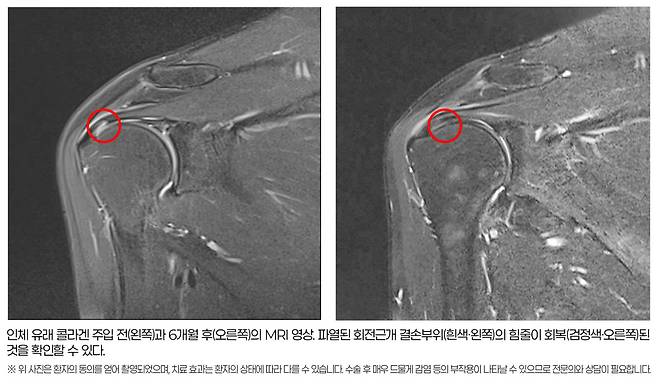

6개월 후 MRI 분석 결과, 회전근개 손상 지표인 신호강도의 호전 및 파열 부위의 재생이 1mm 이상 나타난 환자가 83.33%(25/30명)에 달했다. 파열 부위가 2mm이상 감소한 환자도 26.66%(8/30명)를 차지했다. 심한 염증을 나타내는 체액저류 현상이 환자의 절반 이상인 53.55%(16/30명)에서 유의미하게 감소했다.